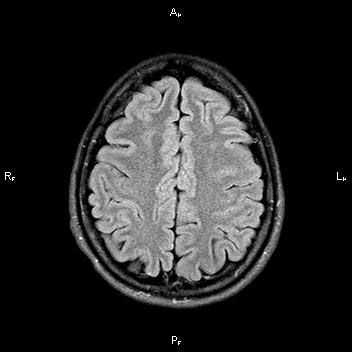

На МРТ головного мозга показаны лакунарные инфаркты в базальных ганглиях (вверху) и в белом веществе паренхимы головного мозга (внизу).

Компьютерная томография (КТ) головного мозга позволяет обнаружить большинство супратенториальных лакунарных инфарктов. Магнитно-резонансная томография (МРТ) головного мозга чётко выявляет как супра-, так и субтенториальные инфаркты (лакуны размером 7 мм и более), а также распространение в серое вещество кортикальной поверхности малого инфаркта в области белого вещества мозга. Такое распространение является преимущественно следствием эмболии, а не сужения просвета (окклюзии) мелких пенетрирующих сосудов. Поэтому в подобных ситуациях не следует ставить диагноз лакунарного инфаркта.